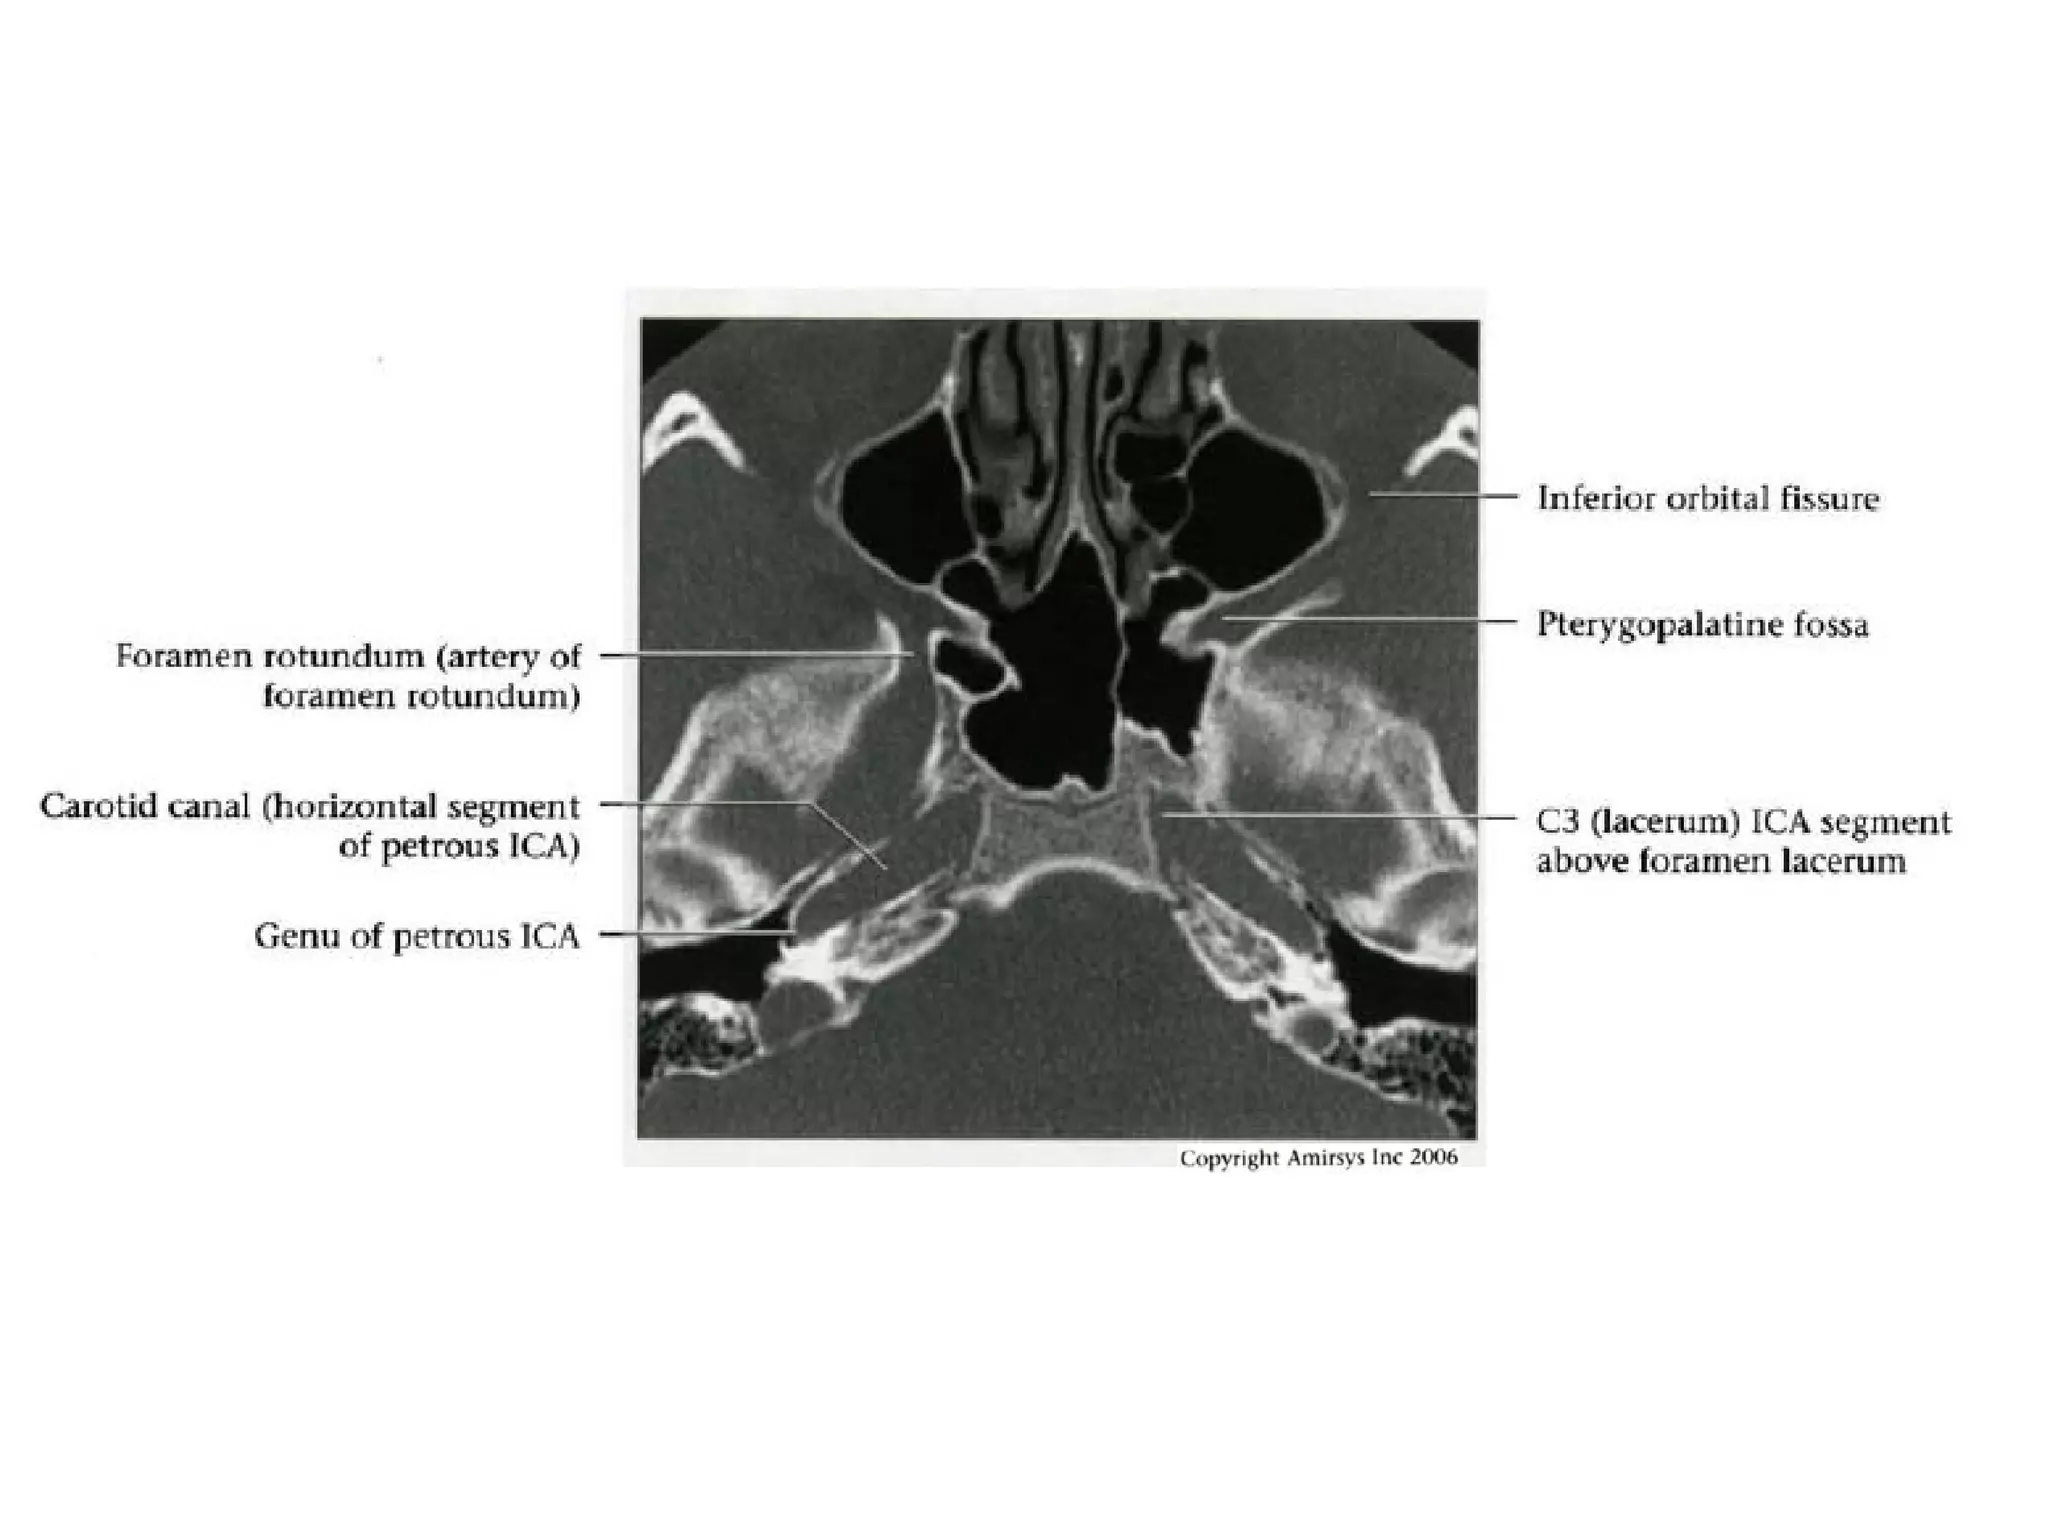

Petrous (C2) segment

• Contained within carotid canal of temporal bone

- Surrounded by extensive sympathetic plexus

- Two C2 subsegments joined at genu

• Short vertical segment - anterior to internal jugular vein

(lJV)

• "Genu" (where petrous ICA turns anteromedially in front

of cochlea)

• Longer horizontal segment

- Exits carotid canal at petrous apex

- Branches

• Vidian artery (artery of pterygoid canal)

anastomoses with external carotid artery (ECA)

• Caroticotympanic artery (supplies middle ear)

Lacerum (C3) segment

• Small segment that extends from petrous

apex above foramen lacerum, curving

upwards toward cavernous sinus

• Covered by trigeminal ganglion

• No branches

Cavernous (C4) segment

• Three subsegments joined by two genus (knees)

- Posterior vertical (ascending) portion

- Posterior (more medial) genu

- Horizontal segment

- Anterior (more lateral) genu

- Anterior vertical (subclinoid) segment